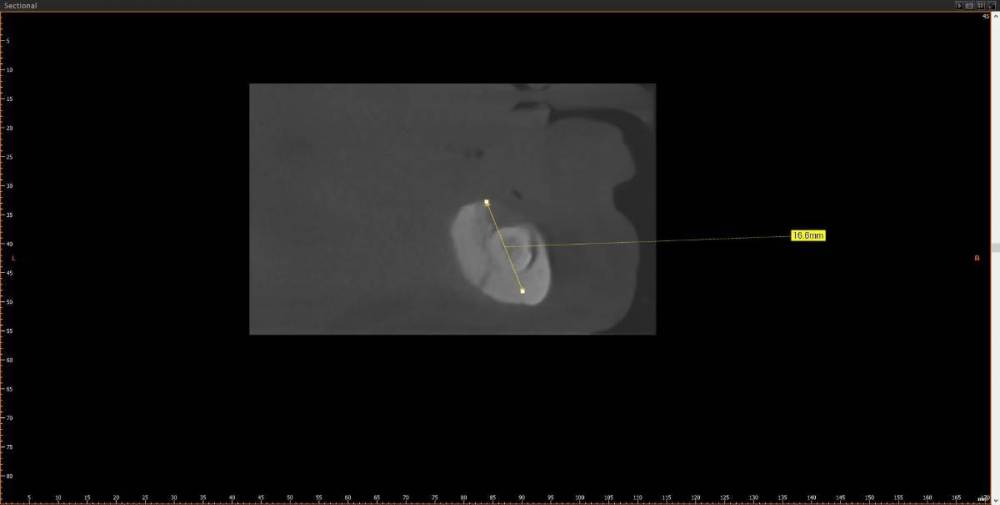

kriokov Опубликовано 10 августа, 2023 Поделиться Опубликовано 10 августа, 2023 ретенция клыка справа. кость 1 тип. Выход нерва почти по вершине. Сьемник не держится. М- 70 лет. Здоров. Нужен совет по установке имплантата справа под локатор, без удаления клыка. Слева штатно. Ссылка на комментарий

kriokov Опубликовано 12 августа, 2023 Автор Поделиться Опубликовано 12 августа, 2023 Вариантов не много. Поговорю с пациентом. 1. Склоняюсь к тому, что предложу установить имплантат в позиции, где он апикально в корне ретенированного. 2. менее предпочтительно из за травматизма- удаление клыка, имплантация 3. установка имплантата по косой сразу за выходом нерва, есть возможность миновать корень , направление имплантата так себе. Спасибо всем за обсуждение. 6 часов назад, Irouil сказал: Фиброзный пульпит будет и все, что такого? удаляли 36, пилили медиальный корень, hit root 35 в нижней трети (видимо потеряли визуализацию в ране + корень с изгибом в сторону 36), внешняя резорбция корня 35 через пару лет, пульпа сдохла, эндодонтия , теперь наблюдаем. Ссылка на комментарий

annda Опубликовано 13 августа, 2023 Поделиться Опубликовано 13 августа, 2023 (изменено) Предположу, что это должны быть как раз первые 4- 6 мм имплантата , корональная его часть( как при синус лифтинге том же) . в данном кейсе ( на втором соезе, что показан) совсем же другая ситуация. В этом ракурсе можно срез посмотреть не через коронку клыка, а через апикальную треть корня, над которым как раз и лежит массив своей губчатой кости.Посмотреть, сколько его там. А самый первый срез чем не устраивает ?Там область за местом выхода СНП или я не понимаю чего-то? Изменено 13 августа, 2023 пользователем annda Ссылка на комментарий